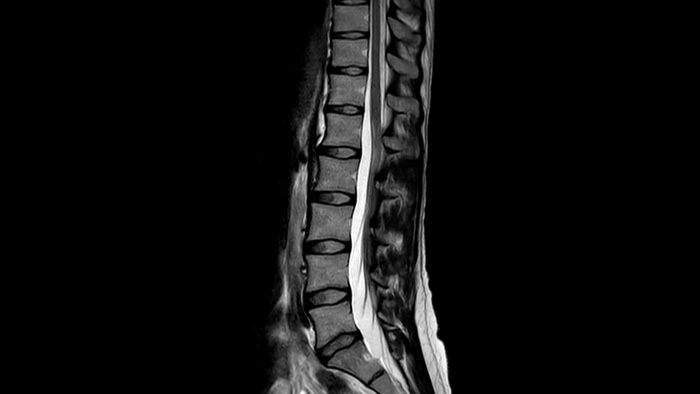

Wondering how to make your MR services more predictable, productive and cost-effective? Helium-free MR operations are the way forward. Helium is a finite resource, this can add extra complexity and unpredictability to your MR operations and budget. That’s why we developed the revolutionary BlueSeal magnet. Based on a decade of innovation, it operates with only seven liters of liquid helium, instead of the usual 1,500 liters. It is fully sealed, freeing up your MR operations from potential helium complications. On top of that, the Ingenia Ambition 1.5T ensures high-quality scanning, reliable performance and easy siting. Are you ready for this new reality in MR?

Philips BlueSeal magnet uses a highly efficient, new micro-cooling technology. It is fully sealed, so no helium can escape,2 either suddenly during a loss of field or gradually. This can have a dramatic impact on the continuity, security and cost of your MR operations.

The Ingenia Ambition 1.5 Tesla magnet is the next generation of MR technology. It brings together the most important aspects of having a successful MR system.